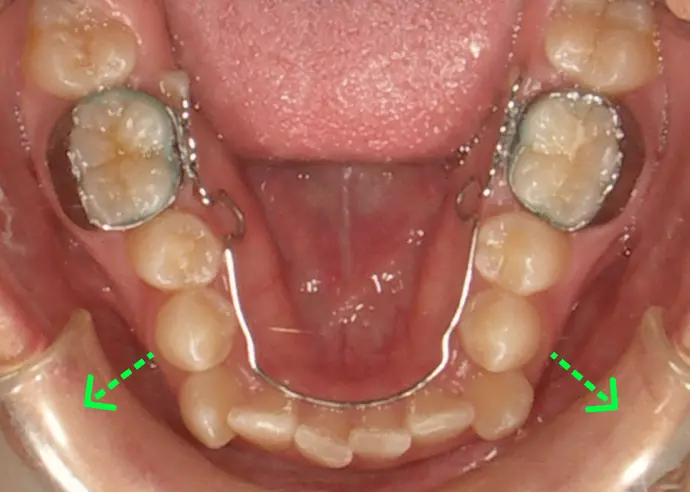

下の歯は歯列を横に広げられる(緑の矢印)と判断した。